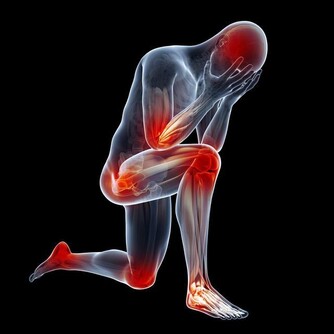

1. 肌肉痙攣

當人體處在缺水狀態時,肌肉無法有效地接受大腦所傳輸的神經信號;腿部肌肉發生這類情況的概率更高,表現症狀便是小腿或大腿抽筋。鍛煉強度過高,沒有及時補充水分時,肌肉中還會出現電解質失衡的情況。如此一來不僅會導致肌肉痙攣,還會增加鍛煉之後出現肌肉酸痛的風險。